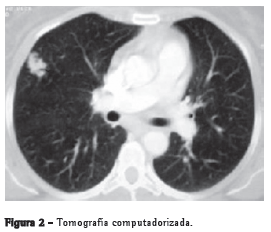

A tomografia computadorizada de tórax demonstrou opacidade nodulariforme, com densidade de partes moles, apresentando contornos lobulados e limites bem definidos, medindo 2,0 x 1,5 cm, localizada no segmento lateral do lobo médio. Ausência de linfonodomegalia mediastinal (Figura 2).